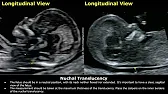

How to Measure Nuchal Translucency (NT) On Ultrasound | First Trimester NT Screening | Fetal USG

Dr. Sam’s Imaging Library51